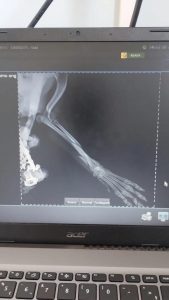

O caso do cãozinho Toby, atacado por um pitbull no bairro Dois Lajeados, em Roca Sales, se agravou novamente. Além dos ferimentos graves, ele foi diagnosticado com fraturas em duas patas e precisou passar por duas cirurgias, o que elevou o custo do tratamento para cerca de R$ 4 mil.